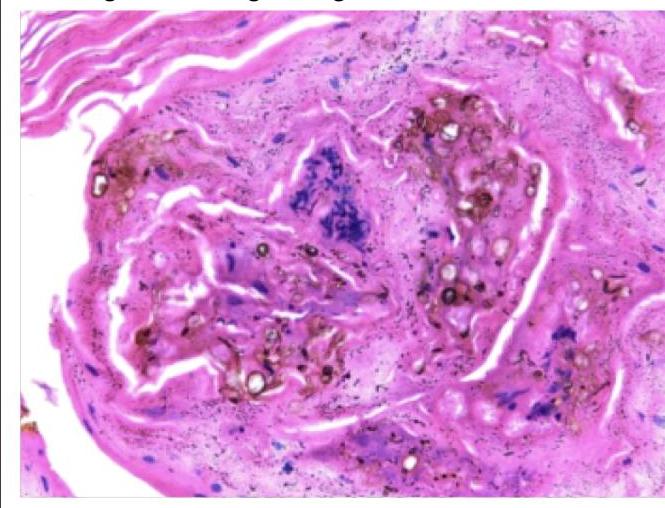

A forest worker developed skin lesions over the forearm, which initially started as macules but then became nodules. Histology of the nodule shows the following findings. Which of the following is true regarding this condition?

Explanation: The image displays **chromoblastomycosis**, a fungal infection characterized by **medlar bodies** or **sclerotic bodies**. These are thick-walled, septate, dematiaceous (pigmented) fungal cells that resemble copper pennies. The patient's history of being a forest worker with skin lesions progressing from macules to nodules is consistent with this diagnosis as it's often associated with **traumatic inoculation** from contaminated plant material. ***It is a dematiaceous fungus*** - The image shows **"copper pennies"** or **sclerotic bodies**, which are characteristic of dematiaceous (pigmented) fungi causing chromoblastomycosis. - These fungi contain **melanin** in their cell walls, which contributes to their characteristic dark appearance. - Common causative agents include *Fonsecaea pedrosoi*, *Phialophora verrucosa*, and *Cladophialophora carrionii*. *Angioinvasion is common especially in people with hemolytic anemia* - **Angioinvasion** is not a feature of chromoblastomycosis, which typically remains confined to the **skin and subcutaneous tissue**. - Angioinvasion is characteristic of **mucormycosis** and **aspergillosis**, particularly in immunocompromised patients, not chromoblastomycosis. *These bodies are formed by engulfment of the dead fungi by the macrophages* - The **sclerotic bodies** are **living fungal cells** in their tissue-specific form, not dead fungi engulfed by macrophages. - They are a distinct morphological form of the fungus, adapting to growth within the host tissue, and are **actively pathogenic**. - These thick-walled structures allow the fungus to persist in tissue and resist host defenses. *Infection commonly spreads to involve tendon, muscle and bone* - Chromoblastomycosis causes **chronic, localized infections** primarily of the **skin and subcutaneous tissue**. - While local tissue destruction can occur, **deep invasion** into tendons, muscles, or bones is **rare** and occurs only in severe, long-standing cases. - The infection typically remains confined to cutaneous and subcutaneous layers without dissemination.